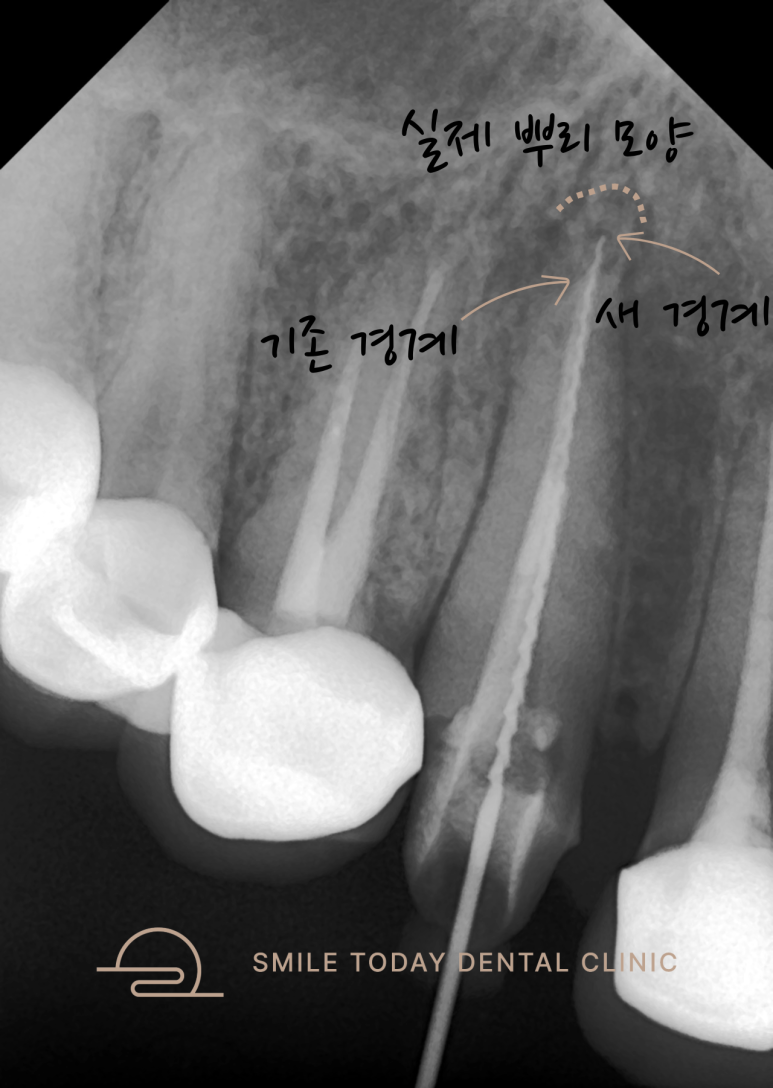

중간 확인을 위해 엑스레이를 촬영하고,

**신경치료용 파일(file)**을 삽입하여

경로와 깊이를 정밀하게 조정했습니다.

이 단계에서는 눈보다 손끝의 감각이 더 중요합니다.

포스트와 치아의 경계면을 구분하며 진행합니다.